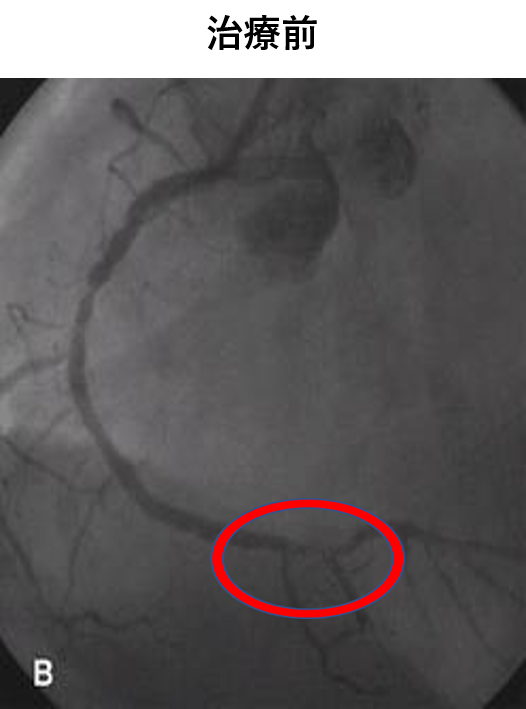

経皮的冠動脈インターベンション(PCI)は、脚の付け根や腕、手首などの血管から、カテーテルという医療用の細く柔らかいチューブを差し込んで、冠動脈の狭くなった部分を治療する方法です。

また、冠攣縮性狭心症の診断や、これまで診断がつかなかった微小循環障害による狭心症においても評価が可能です。

高度石灰化病変を伴う症例へのDebulkingデバイスを使用し、治療を行います。

急性冠症候群においては、救急搬送から再還流まで緊急対応が可能な体制を整えています。

お薬で症状や心電図の改善がない、または乏しい場合に心臓カテーテル検査を行い、高度な狭窄があれば、治療を行うことが一般的です。